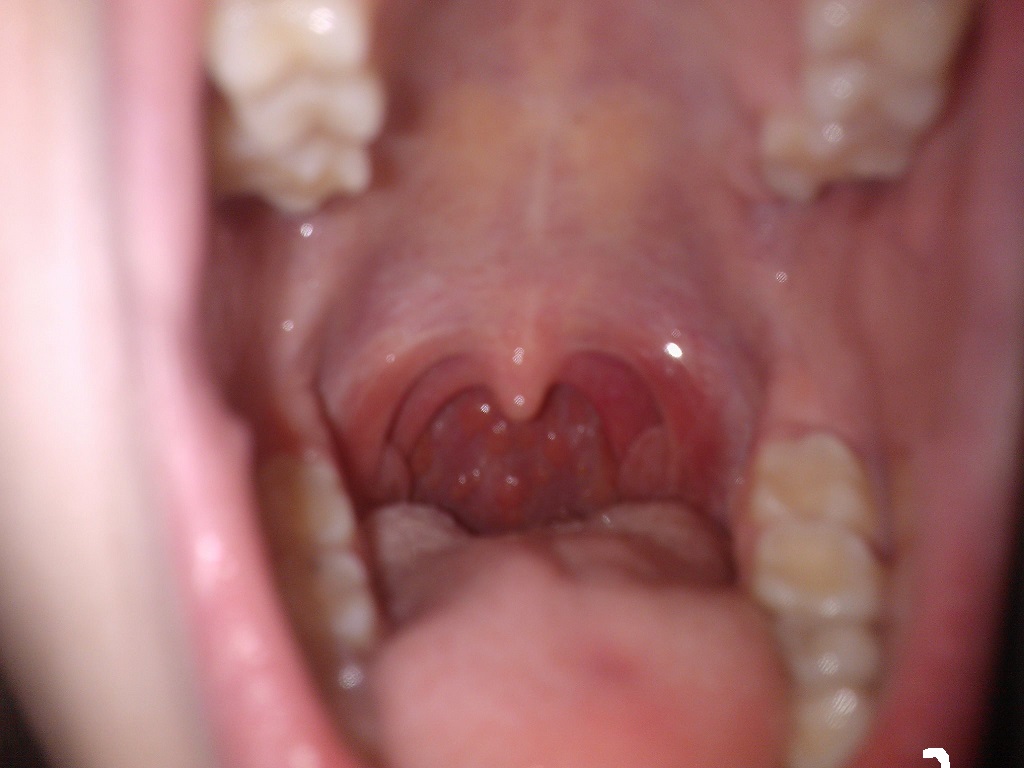

Ahojte mám bolesti v hrdle,nerada chodím k lekárovi a nechcem tam isť "zbytočne" a prosím poradte či je to nevyhnutné.Nemám teplotu som takmer fit len ma bolí hrdlo nič iné už asi 3 dni.Možno je to nechutné ale pridám foto.Nestretli ste sa stým čo to je také malé pľuzgieriky bez hnisu.Dakujem :))